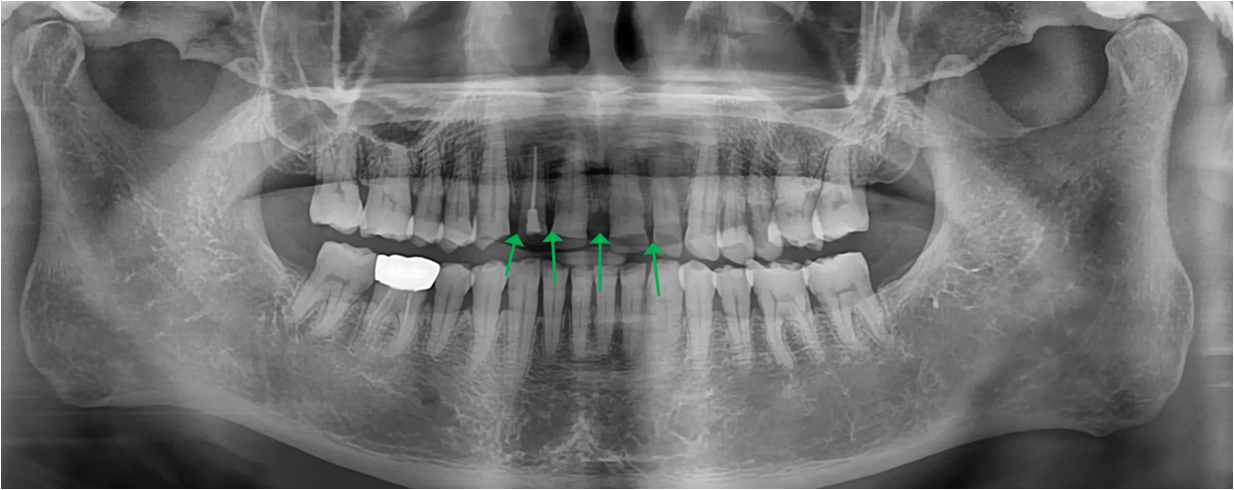

치료 전 파라노마

엑스레이 검사 결과, 치아 사이 벌어짐이 더욱 잘 관찰되었습니다.

마모가 심해지면서 치아 내 신경이 가까워지기 때문에 치아가 시린 현상

또는 통증이 발생할 수 있었습니다.

신경치료를 진행하여 시린현상을 없애고 마모를 막기 위해 크라운 치료를 하였습니다.